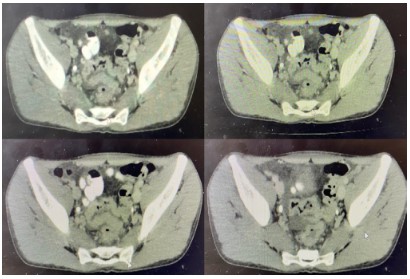

Abdominal X-ray showed a well-defined radiopaque focus seen at the right hypochondriac region in keeping with gallstone. There are loops of dilated small bowel with stacked coin appearance seen at the lower abdomen. There is another radiopaque focus seen projected over the right sacral alar suggestive of gall stone ileus (Figure 1).

Figure 1: Well-defined radiopaque focus seen at the right hypochondriac region and at the right sacral alar.